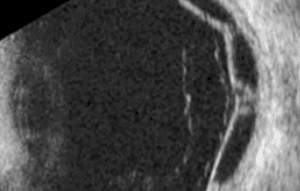

Опухоль сосудистой оболочки и отслойка сетчатки Отслойка сетчатки